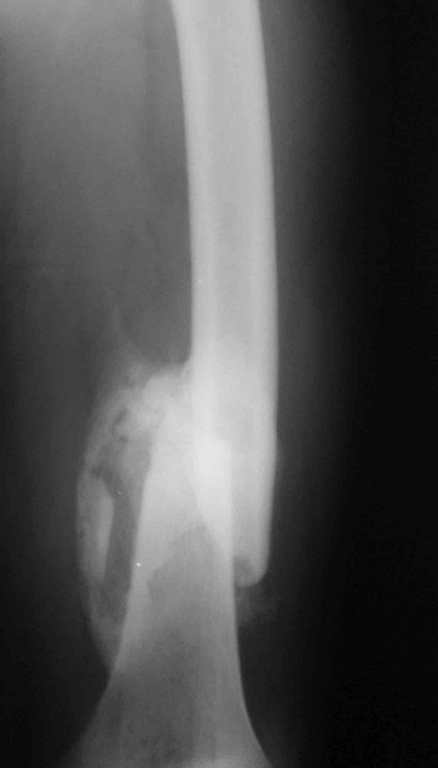

Re: 32- летний пациент с переломами обоих бедер по

Иллюстрации к сообщению